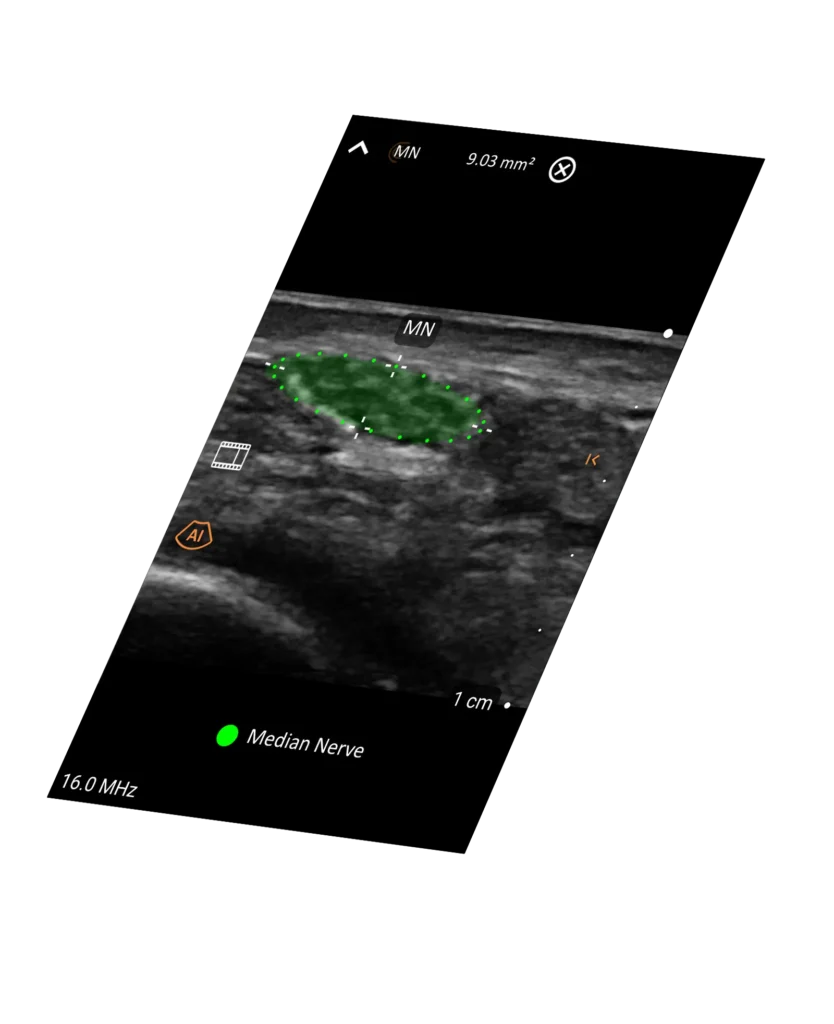

T-Mode™ teaches as you scan. Instantly see labeled anatomy, so even novice users can interpret images and make decisions with confidence.

Key anatomical structures are automatically highlighted and labeled to reduce interpretation time.

Clarius Intelligence combines smart tools and automation to streamline scanning and keep you focused on your patient.